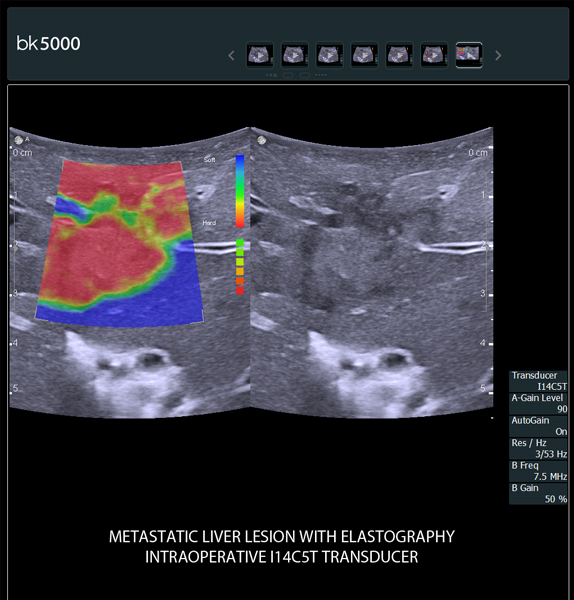

- Ngoài ứng dụng hình ảnh siêu âm chẩn đoán thông thường thì Đặc biệt được sử dụng trong phẫu thuật:

+ Điều trị Hủy u gan dưới hướng dẫn của siêu âm: Bằng sóng cao tần (RFA), Microwave ablation, sinh thiết gan, chọc hút dẫn lưu gan...